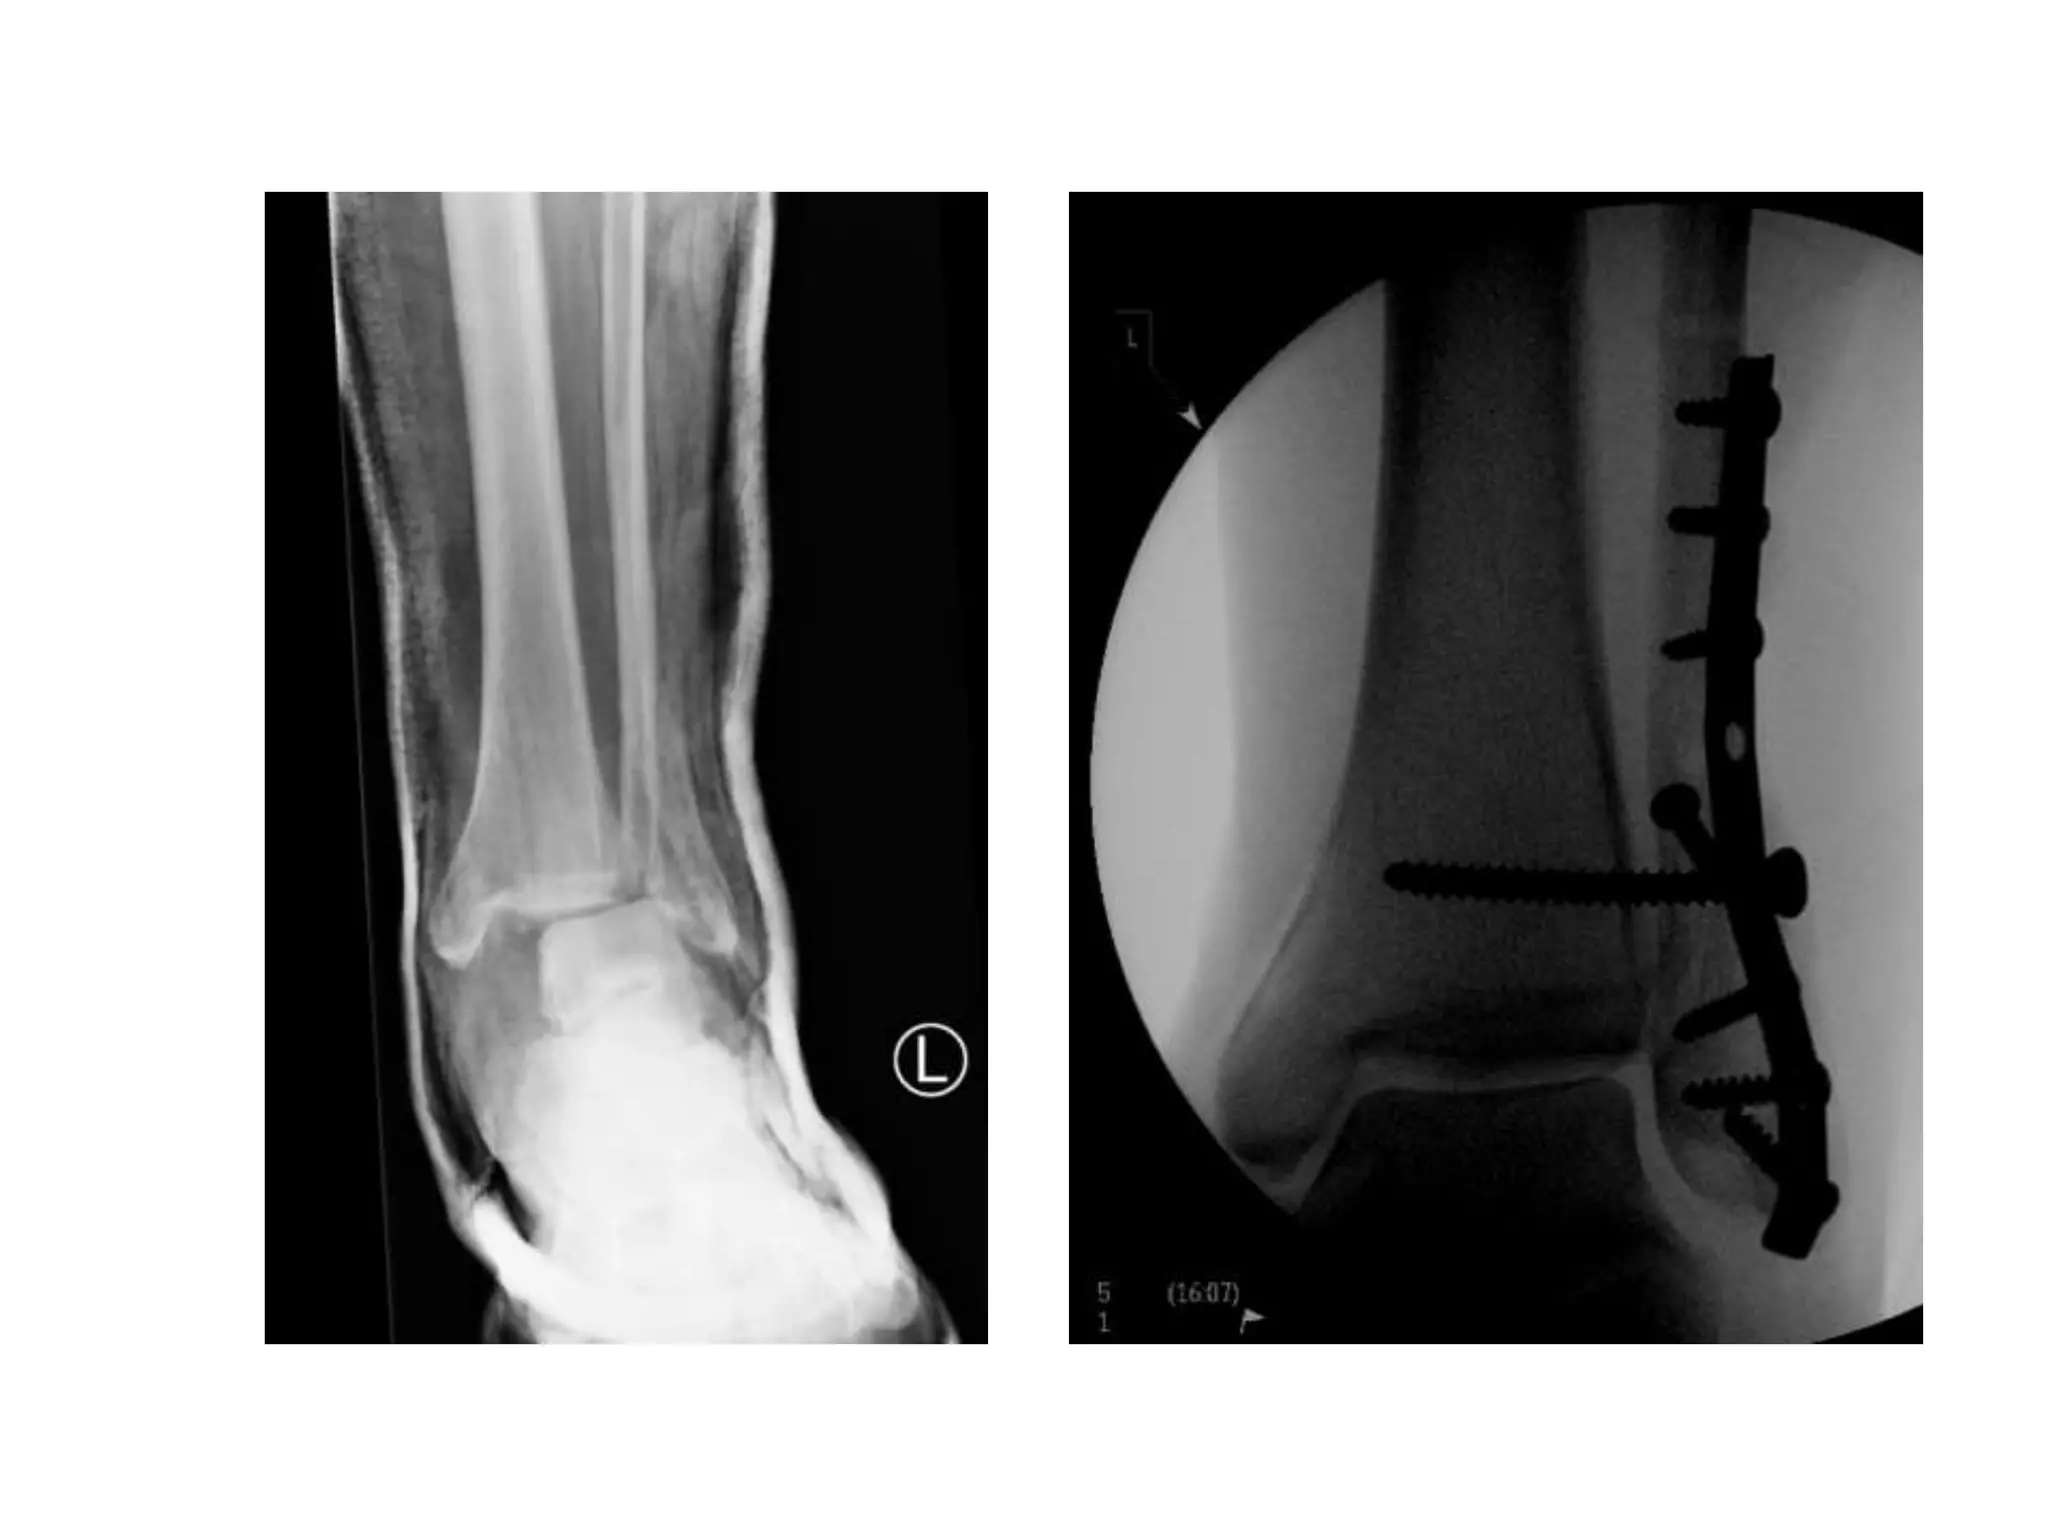

• Isolated Medial Malleolar

• Isolated Lateral Malleolar

• Isolated Posterior Malleolar

• Bimalleolar

• Trimalleolar

• Syndesmotic Injuries

• Dislocations

• Plafond/pilon

Ankle Fractures

• Unimalleoli: 70%

• Bilmalleolar: 20%

• Trimalleolar: 7%

• Open: 3%

Incidence

• Cast if undisplaced with no talar shift

• Fix if displaced

• Check the knee x-ray

Isolated Medial

Lateral

Type A: Fracture of the fibula below the level

of the syndesmosis

Type B: Fracture of the fibula at the level of the

syndesmosis

Type C: Fracture of the fibula above the level

Affects joint in all planes

Interosseous disruption

Often associated with posterior fracture

• Below the level of syndesmosis

• Generally treat in plaster or CAM 6/52 FWB

Weber A

• At the level of syndesmosis

• ORIF if any talar shift or displacement >2mm

• ORIF is medial structures not intact (functional

bimalleolar fracture)

• Lag screw fixation with neutralising plate

Weber B

Fracture Dislocation

• Principles in Management

– Early reduction and stabilisation

– Cast / ex-fix or ORIF if swelling appropriate

(usually <6hours or >6 days)